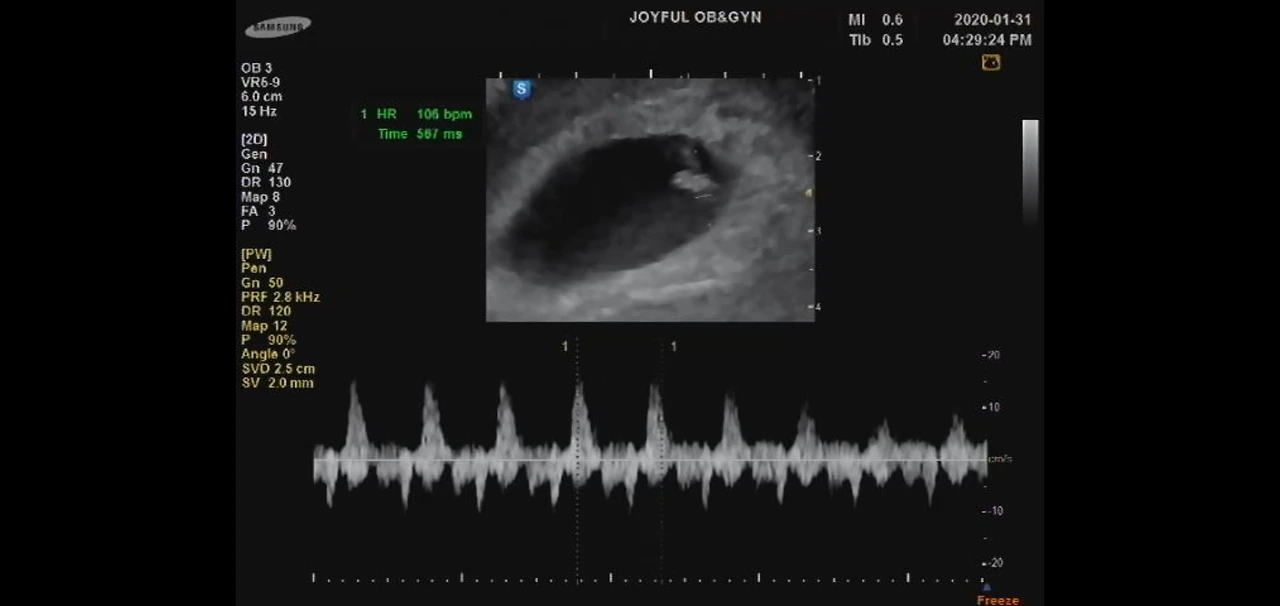

아기의 존재를 처음 알게 되었던 순간이 선명히 기억난다. 초음파실에서 아기의 심장 소리를 듣자 진짜 엄마가 된 나를 실감했다. 병원에서는 초음파에서 아기집이 보이더라도 아기의 심장 소리를 들어야 임신확인증을 내어준다고 했다. 그렇구나. 인간이라는 존재의 시작이 심장 움직임으로부터 시작되는 구나. 병원을 갈 때마다 가장 좋은 시간이 바로 아기 심장 소리를 들을 때다. 임신 초기에는 의사가 아기의 몸 구석구석 위치를 알려주는데도 어디가 어딘지 알아보기 힘들었다. 꼬물꼬물 귀엽게 움직이는 아기의 움직임에 비해 심장소리는 선명하고 웅장하게 진료실에 울려퍼진다. 녹화된 영상을 몇 번이고 돌려보며 그 경이로운 소리를 온 몸으로 느껴본다. 깊은 첼로소리 같이 아름답다.

그런데 이상하다. 오늘은 아기의 심장 소리가 아니라 내 심장 소리를 듣고 있다. 처음 느끼는 감정과 경험이다. 아기의 심장 소리를 듣고 처음으로 진짜 엄마가 됐구나 깨달았던 그 날처럼, 나의 심장 소리를 듣고 내가 나의 주인이라는 것을 깨달았다. 이 깊은 첼로 선율 같은 심장 소리가 나라는 존재를 증명해 준다.

“건강하시네요. 임신 때문에 숨쉬기 힘든 거고 출산까지 조금만 참아보세요” 병원에 다녀온 후에도 한동안 귓 속 달팽이관에 내 심장 소리가 쿵쿵 들리는 것 같았다. 배 위에 손을 얹고 눈을 감는다. 옅게 아기의 심장도 함께 느껴지는 것 같다. 내 몸 안에 두 개의 심장이 함께 뛰고 있다. 엄마는 아기의 심장을 느끼며 엄마가 된다. 엄마의 힘차게 뛰는 심장은 아기의 심장이 된다.